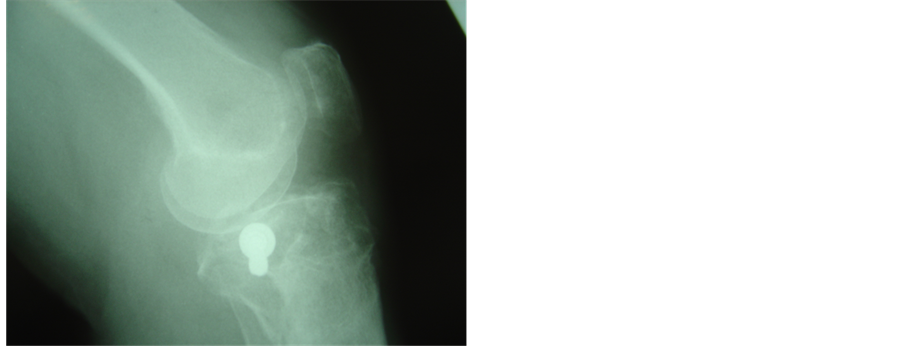

In three of our cases a hybrid fixator could not be used because of previous tibial shaft fractures that had been treated with open reduction and internal fixation―the presence of metal ware forbidding application of peripheral pins. In these cases, we chose to combine canulated screws with an anatomic lateral plate. Here, the canulated screws were applied open, through a lateral incision, but extremely close to the articular surface to allow correct positioning of the anatomic locking plate. The knee was once more not opened and the plate applied to unite the condyles to the shaft. Careful correction of varus-valgus malalignement and accurate canulated screw positioning were always checked with the II (Figures 3(a)-3(d)).

Figure 3. (a), (b): Schatzker VI fracture. Pre operative X-rays AP and Lateral; (c), (d): The fracture was treated with combination of canulated screw and anatomic locking plate because of presence of previous metal ware. Post-operative X-rays AP and lateral.